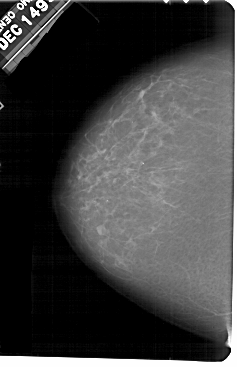

A_1601_1.LEFT_MLO

LEFT_CC LINES 5491 PIXELS_PER_LINE 3541 BITS_PER_PIXEL 12 RESOLUTION 43.5 NON_OVERLAY

LEFT_MLO LINES 5251 PIXELS_PER_LINE 3406 BITS_PER_PIXEL 12 RESOLUTION 43.5 NON_OVERLAY